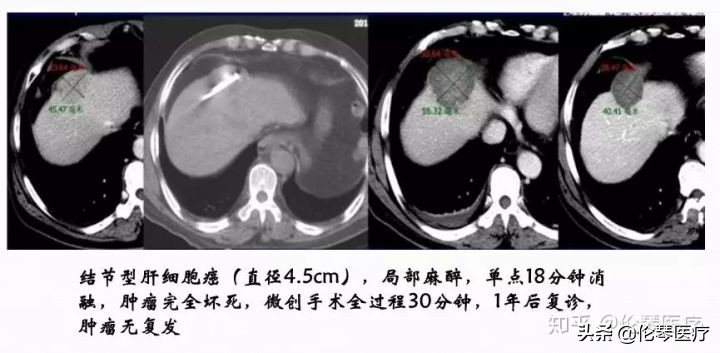

这是一个典型的微波治疗肝癌患者的案例。肝脏内比较大的肿块,接近5cm左右,我们通过8个位点做消融治疗,取得比较好的效果,术后肿瘤完全坏死。